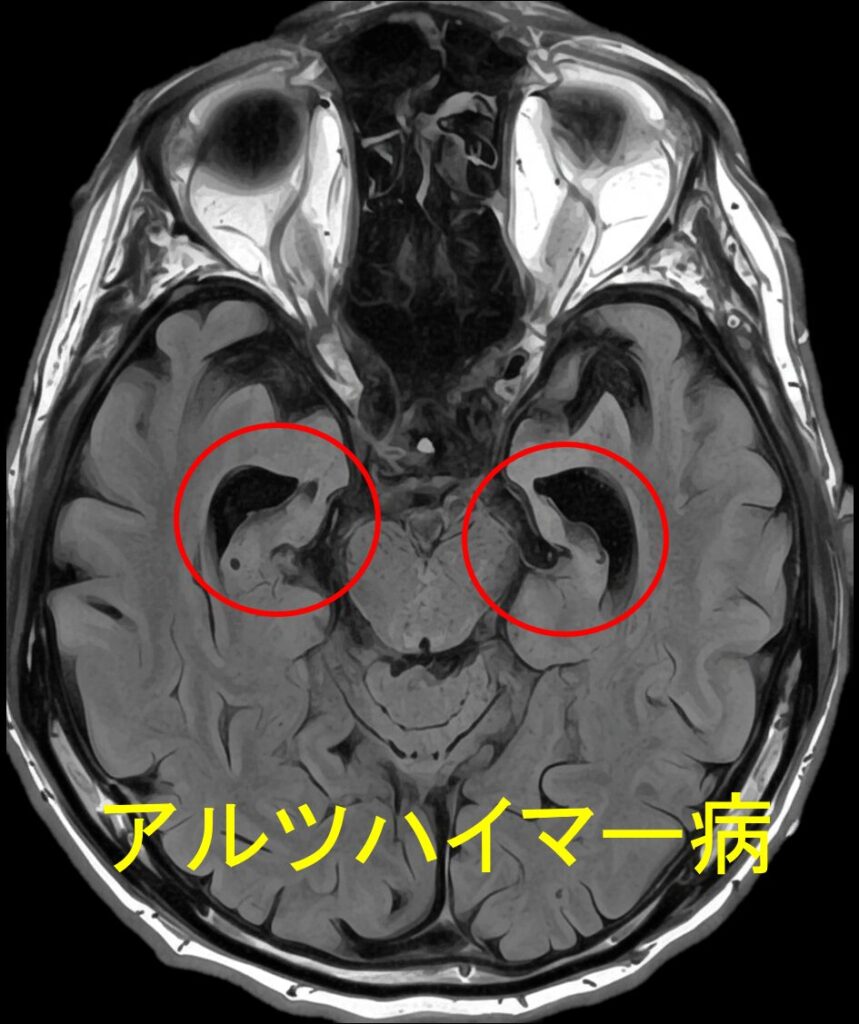

脳萎縮のMRI診断:専門医による評価の視点と検査

MRI検査は、脳の萎縮状態を客観的に確認するために不可欠です。専門医は以下の点を複合的に観察し、萎縮のタイプと原因を推測します。当院では当日MRI検査が可能です。

萎縮の場所とパターンから病態を特定する視点

- 海馬周辺の萎縮: アルツハイマー型認知症の初期に強く現れる萎縮パターン。

- 脳全体・脳室の拡大: 加齢やアルコール多飲、または血管性障害による広範囲な萎縮。脳室の拡大も確認される。

- 脳溝の広がり: 脳の溝(脳溝)が深く広がっているかを確認。

微小梗塞・白質病変の所見が多い場合、血管性脳萎縮が強く疑われます。この場合、高血圧や糖尿病などの生活習慣病の管理が非常に重要になります。

海馬に萎縮が見られる

脳溝は深く広がっている

当院では、海馬の萎縮度を客観的に数値化するVSRAD解析を脳ドックに組み込んでいます。MRI画像からわかる認知症のサインについて詳しくは、【脳ドック×VSRAD解析】MRIでわかる認知症のサイン|50歳からの備えにもご覧ください。